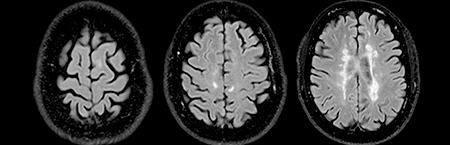

• Ressonância magnética

Ressonância magnética

• "aumento do número de lesões supratentoriais (…) no estudo medular não se destacam seguras lesões de novo"